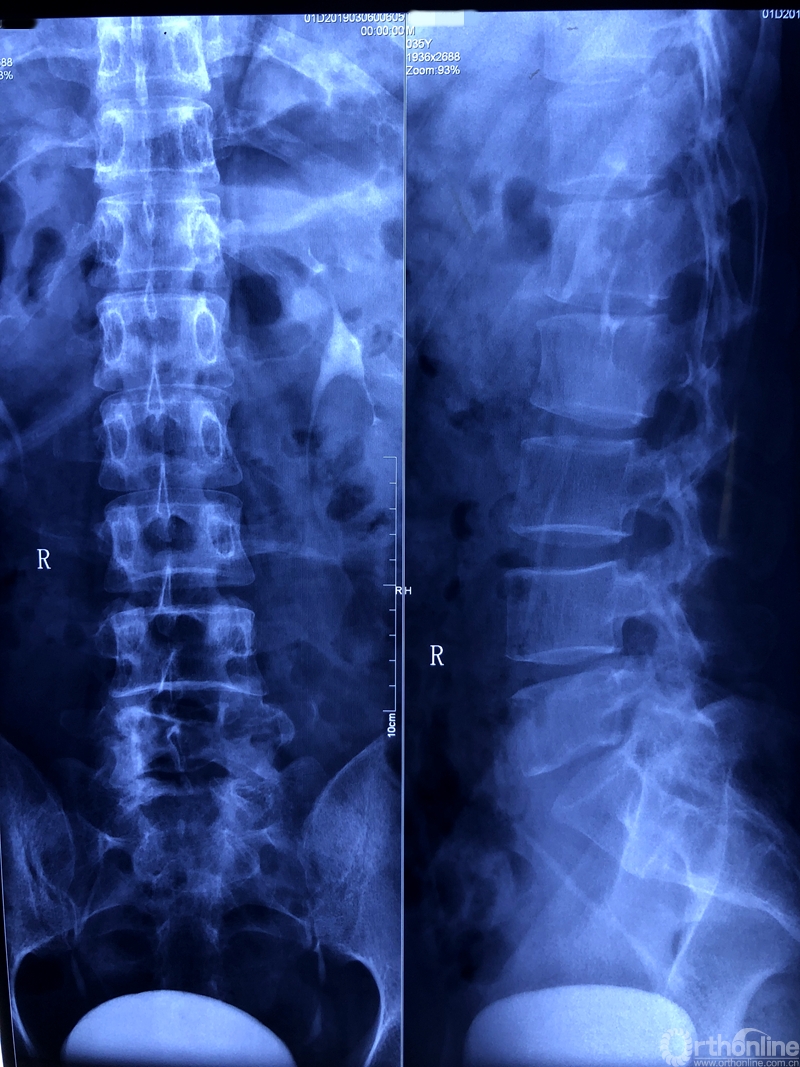

通过对患者详细的身体检查、穿刺活检和综合评估后,确诊患者是腰椎骨巨细胞瘤,第五腰椎破坏70%以上,邻近软组织也有破坏。这种肿瘤属于交界性的有恶性倾向的良性肿瘤,若不彻底切除,患者疼痛会逐渐加剧,甚至因骨质坍塌而瘫痪,若肿瘤细胞转移更会危及生命。若是能在早期尽快彻底、完全地切除肿瘤及被侵蚀椎体,病人才很可能完全战胜肿瘤。

术前X线片